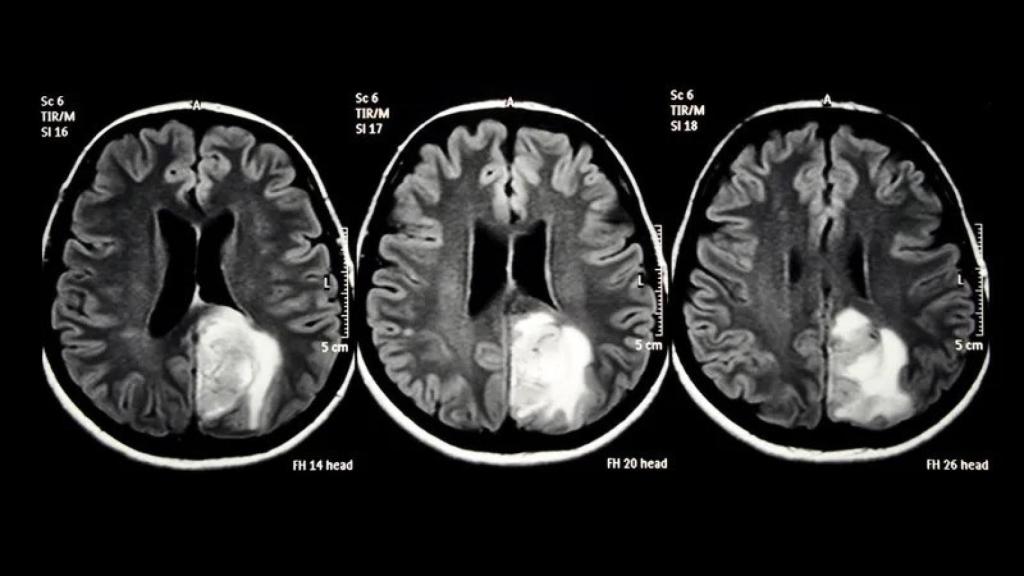

Prueba de imagen en el encéfalo.